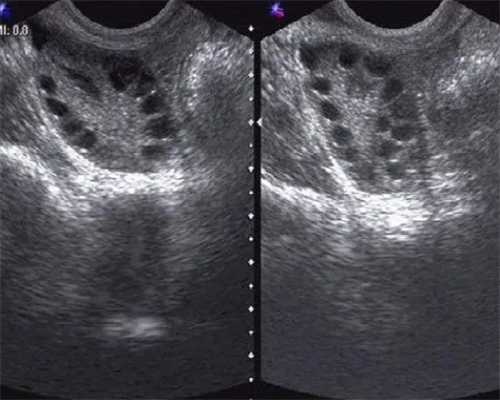

多囊如何备孕多囊卵巢综合征怎么治疗~代生男孩微信群

多囊卵巢综合征的症状是什么?~代生代怀费用

多囊卵巢综合征的症状是什么1、多囊患者治疗一般是服用药物,无...